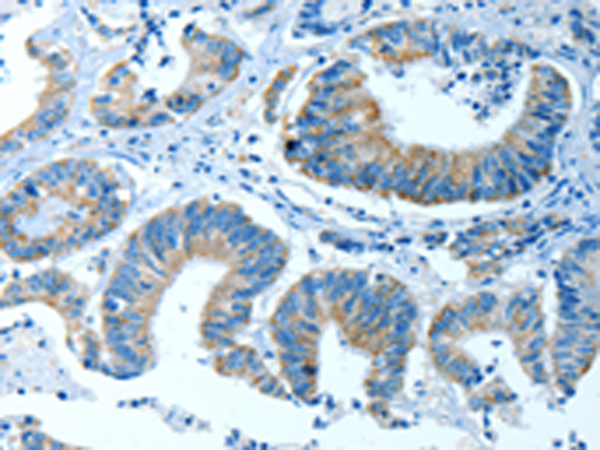

分类: 科研抗体货号: P07837别名: CGI-14应用: WB,IHC反应种属: Human, Mouse, Rat